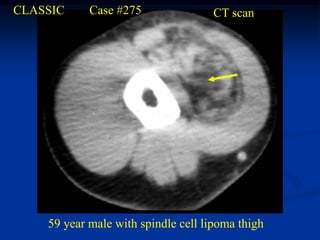

CLASSIC     Case #275               CT scan

59 year male with spindle cell lipoma thigh

Spindle Cell Lipoma The spindle cell lipoma is seen more commonly in men between the ages of 45 and 65 years and is typically located in the posterior neck or shoulder area. MRI imaging demonstrates the high signal features of a lipoma on the T-1 weighted image but with areas of lower signal streaking seen throughout the high signal areas where the fibrous tissue is located. Histologically, the spindle cell lipoma looks like any other lipoma except for the presence of benign- appearing fibrous tissue with occasional areas of gelatinous break- down in the fibrous tissue. The treatment for this variant is a marginal resection and carries a minimal chance for local recurrence.

CLASSIC Case #275 CT scan 59 year male with spindle cell lipoma thigh